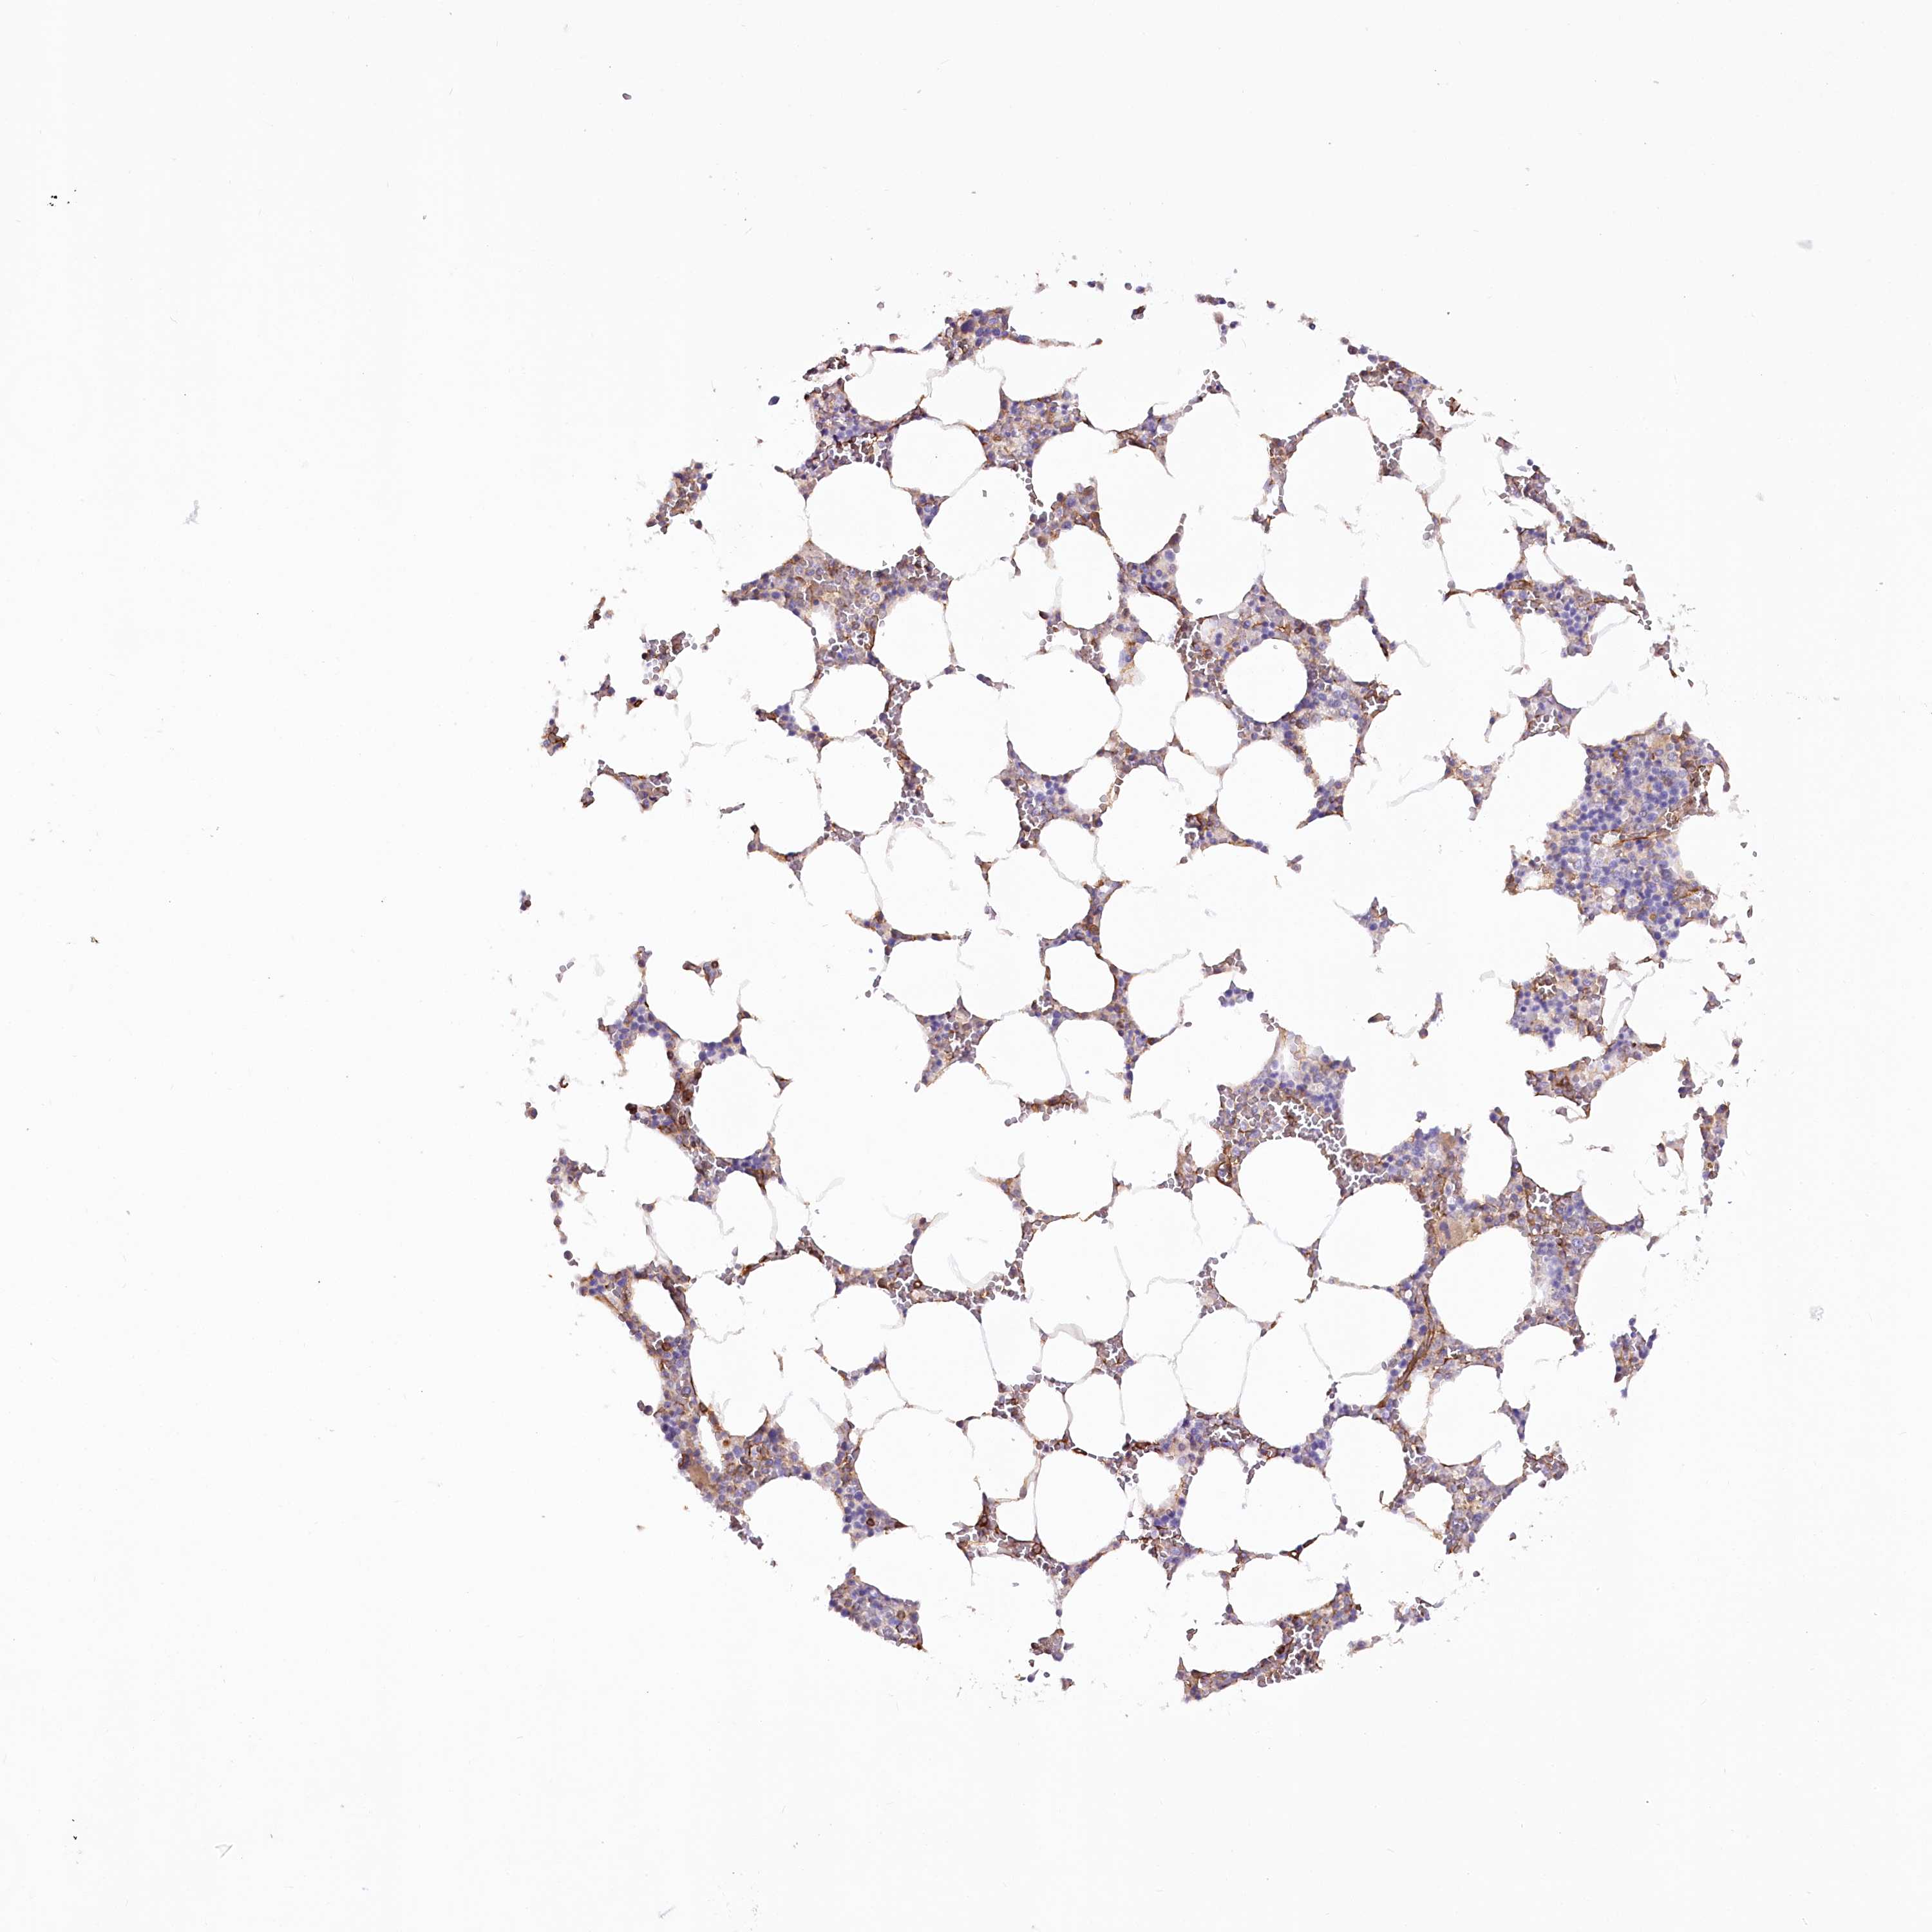

BONE MARROW - Antibody stainingi

Antibody staining in the annotated cell types in the current human tissue is reported as not detected, low, medium, or high, based on conventional immunohistochemistry profiling in selected tissues. This score is based on the combination of the staining intensity and fraction of stained cells. Each image is clickable and will lead to virtual microscopy that enables deeper exploration of all samples and also displays staining intensity scores, fraction scores and subcellular localization as well as patient and tissue information for each sample.

Antibody HPA030665Antibody HPA068563Antibody CAB037231

Hematopoietic cells Not detectedNot detectedNot detected